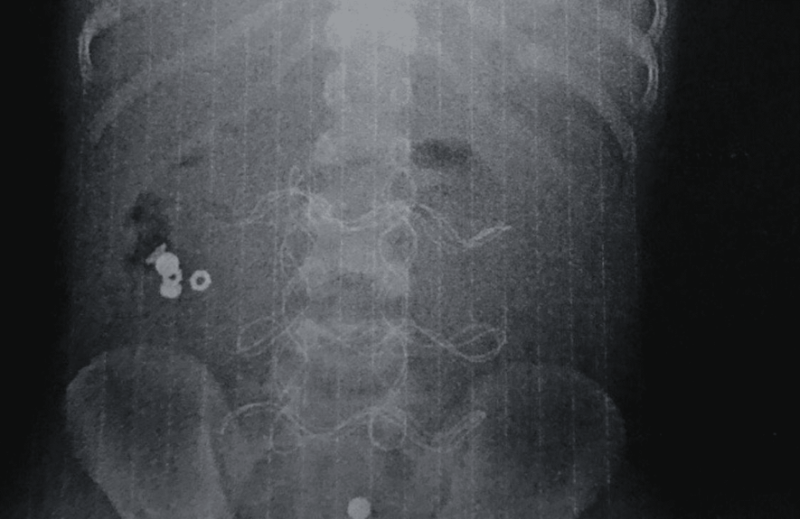

“Поділюся з вами медично складною історією з, на щастя, хорошим кінцем. До нас в ОДКЛ привезли 7-річного хлопчика у вкрай тяжкому стані інфекційно-токсичного шоку з клінікою розлитого перитоніту.

Як виявилось, все через батарейку, яку дитина проковтнула, що спричинило перфорацію тонкого кишківника”, – зазначив Тарас Мельник.

Хлопчику з Прикарпаття провели 3 операції, щоб врятувати після того, як він проковтнув батарейки

Фото: Тарас Мельник